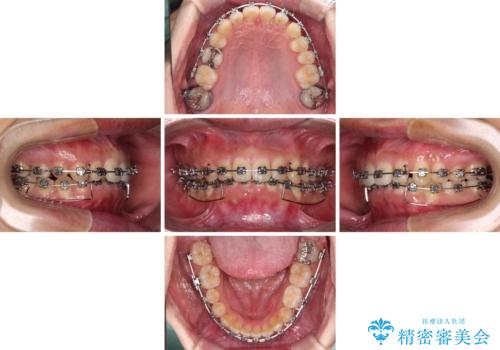

【モニター】前歯に隙間ができるほどのディープバイト ワイヤー装置で負担の少ない咬み合わせに

- 前歯の隙間を気にして来院された患者様です。

下顎前歯が見えなくなるくらいに深い咬み合わせであり、さらに上顎の正中が開くほど下の前歯が突き上げている状態でした。

奥歯は手前に倒れてしまっているため、後方に起き上がらせることで深い咬み合わせ・ディープバイトを改善する必要があります。

ディープバイトの方は項合力が強大であることが特徴のため、仕上がりを重要視して、ワイヤー装置にて矯正治療を行うこととしました。